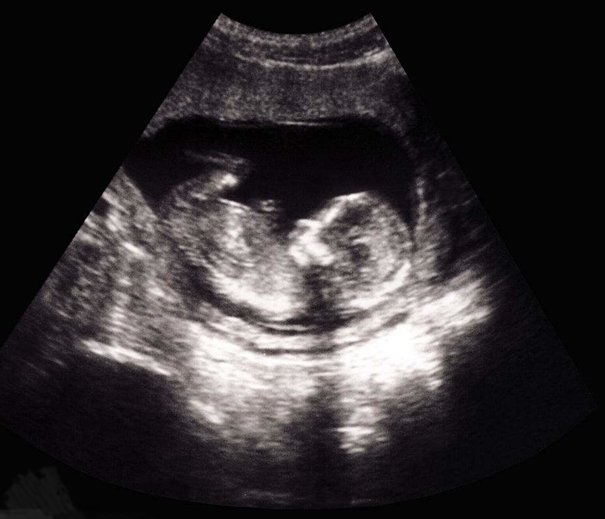

超聲醫(yī)學(xué)由于采用了灰階顯示、實(shí)時(shí)掃描與動(dòng)態(tài)聚焦等手段,因而聲像圖的質(zhì)量顯著提高,直觀、逼真、清晰而富有層次。對(duì)人體心、肝、膽、腎、顱腦、眼球、子宮、乳房及盆腔等,都有很好的診斷價(jià)值。應(yīng)用這種聲像圖,不僅能顯示臟器的外形,而且能深入觀察其內(nèi)部結(jié)構(gòu)。還能定位指導(dǎo)穿刺。從妊娠5周到分娩前胎兒的生長(zhǎng)發(fā)育過(guò)程都能從影像圖中顯示出來(lái),這對(duì)于計(jì)劃生育、檢查胎兒畸形、鑒別性別,都很有意義。診斷時(shí)射入人體的超聲能量很小,一般為10mW/cm2左右,無(wú)致傷作用。已成為一種常規(guī)檢查法。將電子計(jì)算機(jī)技術(shù)引入超聲診斷,產(chǎn)生了超聲CT技術(shù)。它將獲取超聲通過(guò)臟器的傳播時(shí)間及幅度或衰減隨頻率的變化數(shù)據(jù),輸入電子計(jì)算機(jī)里,經(jīng)過(guò)信號(hào)數(shù)字處理和綜合后再給出組織的切面圖像,這種技術(shù)的特點(diǎn)是能得到活體組織內(nèi)部超聲參量的空間分布。對(duì)于1MHz的超聲,切面圖像的分辨力可到5mm。目前已到臨床試驗(yàn)階段。